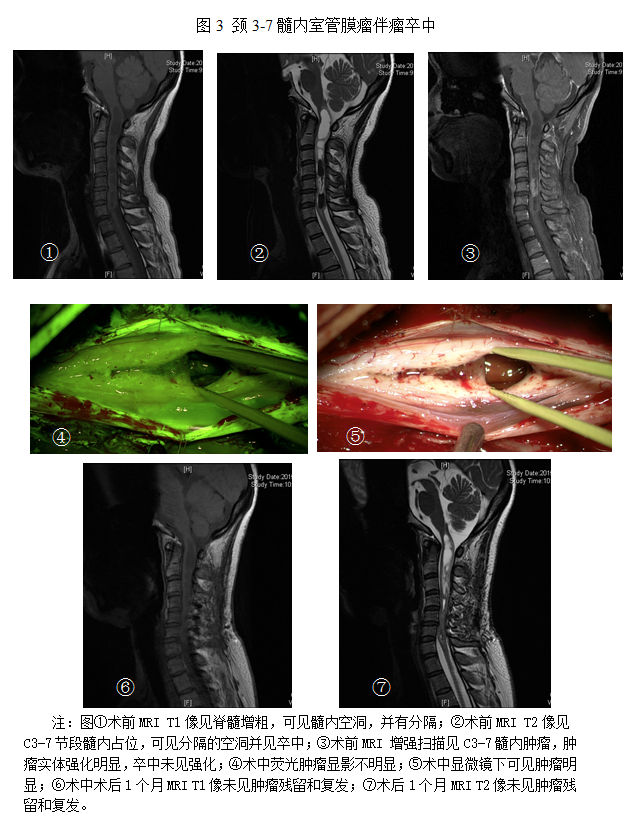

比如下面几张磁共振显示的肿瘤:包括颈/腰椎神经鞘瘤,髓内室管膜瘤等等,最早的症状类似于颈椎病和腰椎病,往往发现较晚,患者肿瘤生长巨大或者出现瘫痪等症状了才来就诊,导致手术难度加大。